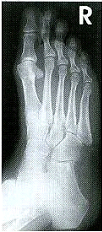

O pé, por inteiro, deve ser demonstrado, incluindo as falanges, os metatarsos e o navicular, os cuneiformes e o cubóide.

O eixo longitudinal do pé deve estar alinhado com o eixo longitudinal da porção do filme a ser exposta. Não há rotação se for evidenciada uma distância praticamente igual do segundo até o quinto metatarsiano. Em geral, as bases do primeiro e do segundo metatarsos são separadas, mas as bases do segundo ao quinto aparecerão sobrepostas. O espaço articular entre o primeiro e o segundo cuneiformes deve ser demonstrado.

O centro dos quatro lados do campo de colimação (RC) deve ser com a base do terceiro metatarso, com as bordas de colimação incluindo os tecidos moles circunvizinhos do pé. Geralmente, as articulações MFs devem parecer abertas. As articulações IFs podem aparecer parcialmente fechadas devido aos raios divergentes.

O contraste e a densidade ótimos se o paciente não tiver se movimentado permitirão a visualização nítida das margens corticais e da trama trabecular das falanges distal e das porções distais dos ossos do tarso até o tálus. (Ver a técnica com kVp mais alta para uma sensibilidade mais uniforme entre as falanges e os ossos do tarso.) . Os ossos sesamóides (se presentes) devem ser visualizados através da cabeça do primeiro metatarso.

A Radiografia terá que ficar parecida com essa: